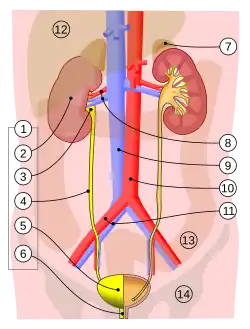

Der Harnleiter beginnt am Nierenbecken, in dem der von der Niere zuerst abfiltrierte und anschließend aufkonzentrierte Urin gesammelt wird. Am Ursprung knickt der Harnleiter um etwa 90° ab. Er läuft dann als Bauchteil (Pars abdominalis) im Retroperitonealraum auf dem gleichseitigen Musculus psoas major.[2][3] Er überquert den gleichseitigen Nervus genitofemoralis und unterquert dann bei der Frau die Eierstockarterie (Arteria ovarica), beim Mann die Hodenarterie (Arteria testicularis).[3] Etwa ab Höhe des fünften Lendenwirbels zieht der Harnleiter leicht zur Mitte hin.[4] Am Beckeneingang biegt er bauchwärts um und verläuft als Beckenteil (Pars pelvica, Synonym: Pars pelvina) in der Wand des „kleinen Beckens“ bis zur Harnblase. Er überkreuzt dabei zunächst die Aufzweigung der Arteria iliaca communis und unterkreuzt dann beim Mann den gleichseitigen Samenleiter, bei der Frau die gleichseitige Gebärmutterarterie (Arteria uterina).[3] Der Harnleiter hat bei Erwachsenen eine Länge von 25 bis 30 Zentimetern, Bauch- und Beckenteil sind etwa gleich lang.[5] Der Durchmesser beträgt 2 bis 7 Millimeter,[6] im Regelfall 3 bis 4 mm. Bei Neugeborenen ist der Harnleiter 6,5 bis 7 cm lang.[5]

Der rechte Harnleiter liegt in räumlicher Nähe zu Zwölffingerdarm, Ileum, Colon ascendens, Blinddarm und Wurmfortsatz, der linke zu Bauchspeicheldrüse, Jejunum, Colon descendens und Colon sigmoideum. Da genaue anatomische Landmarken zur Ortung des Organs fehlen, kann er bei Operationen am Colon und Mastdarm und insbesondere bei der laparaskopischen Entfernung der Gebärmutter versehentlich verletzt werden.[7][8] Die Harnleiter liegen beidseits bauchseitig des Nervus genitofemoralis, der rechte liegt seitlich der unteren Hohlvene (Vena cava inferior), der linke seitlich der unteren Mesenterialvene (Vena mesenterica inferior).[9]

Nach seinem Eintritt in die Harnblasenwand verläuft der Harnleiter zunächst eine kurze Strecke innerhalb dieser Wand (intramural). Dieser intramurale Abschnitt ist 0,5 bis 1 cm lang,[10] nach anderen Angaben 1,5 bis 2 cm.[3] Dann durchbohrt er die Blasenschleimhaut und mündet mit der Harnleitermündung (Ostium ureteris) in das Innere der Harnblase. Die schlitzförmigen Harnleitermündungen sind klappenartig geschlossen, wenn durch sie kein Urin tritt.[3] Der Verlauf in der Blasenwand verhindert bei stärkerer Füllung der Harnblase einen Rückfluss des Urins zur Niere (vesikorenaler Reflux).[11] Die beiden Harnleitermündungen begrenzen mit der unpaaren Harnröhrenöffnung im Inneren der Blase das Harnblasendreieck (Trigonum vesicae).[12]

Drei Abschnitte des Harnleiters sind anatomische Engstellen, in denen sich deshalb bevorzugt Harnsteine festsetzen:[12][13]

- Ursprung aus dem Nierenbecken („ureteropelvischer Sphincter“)

- am Übergang vom großen in das kleine Becken mit Überquerung der Aufgabelung der Arteria iliaca communis

- intramuraler Verlauf in der Harnblasenwand, dies ist die engste Stelle im gesamten Harnleiterverlauf.

Die Blutversorgung des Harnleiters unterscheidet sich aufgrund der Länge des Organs regional. Der nierennahe Abschnitt erhält Blut direkt aus der gleichseitigen Nierenarterie (Arteria renalis). Der mittlere Abschnitt wird von Ästen der Aorta, der Arteria iliaca communis und der Keimdrüsenarterien (Eierstock- bzw. Hodenarterie) versorgt. Das Endsegment erhält Blut über Äste der Arteria iliaca interna. Der Lymphabfluss erfolgt im oberen Harnleiterabschnitt über die rechten und linken Lendenlymphknoten (Nodi lymphoidei lumbales dextri et sinistri), im mittleren Harnleiterabschnitt über die Nodi lymphoidei iliaci communes und im letzten Abschnitt über die Nodi lymphoidei iliaci interni.[14]